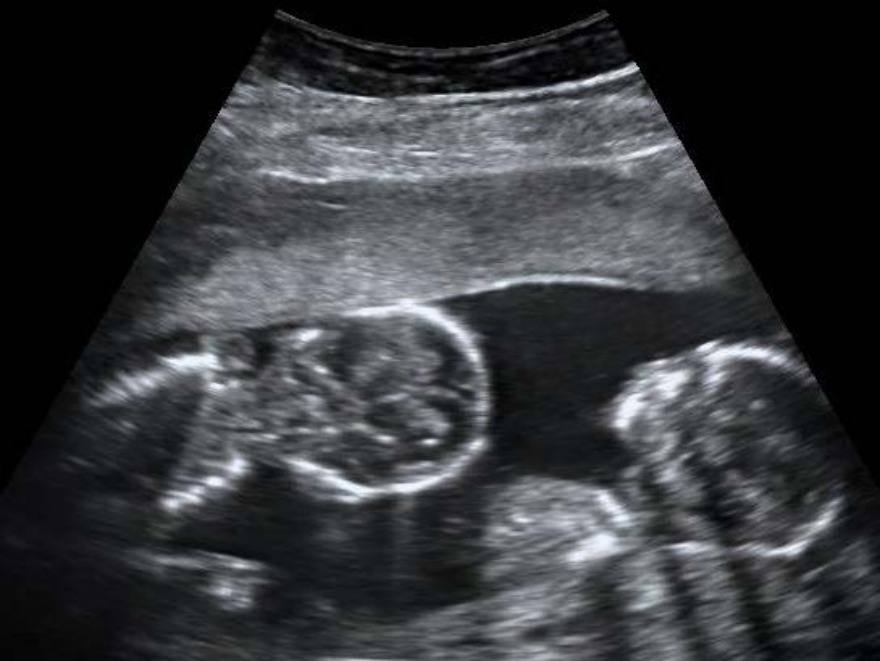

Œn USç examination of a pregnant woman at 1Ž weeks gestation, the following finding was noted. Which of the following events will result in the development of this condition? 50

A) Early blastomere separation

B) Duplication of inner cell mass before amniotic sac formation

C) Duplication of embryonic disc between 4 -è days after fertili‹ation

D) Duplication of embryonic disc between ê - 1‘ days after fertili‹ation

Correct Answer:D

Explanation:

The USG examination is suggestive of monozygotic, monochorionic, monoamniotic

twins. Duplication of the embryonic disc between the 8-12 days after fertilization will result in the development of this condition.

At this stage, the amniotic sac is already formed. In this case, the two fetuses share a common chorion and common amniotic cavity.

The image given below shows a diagrammatic representation of the placentation.